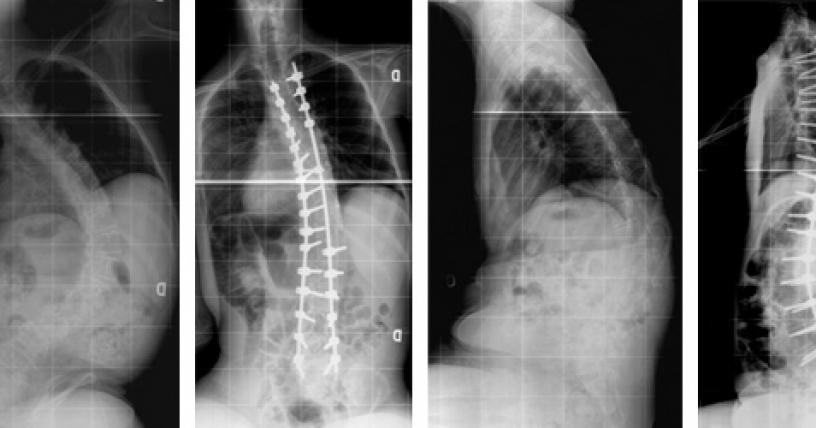

Eso incluye cosas como fisioterapia para mantener los músculos fuertes, terapia respiratoria para mantener la fuerza pulmonar, terapia del habla, terapia ocupacional y cirugía para tratar problemas asociados con la afección, como problemas cardíacos o cataratas, dice el NIH .